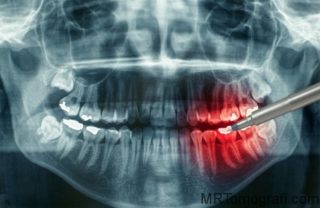

Gömülü olan dişler ağız içine sürme vakti gelmesine rağmen sürememiş, çene kemiği içinde kalmış dişlerdir. Sıklıkla 3. azı dişleri (yirmi yaş dişleri) gömülü kalmaktadır.

Gömülü dişler sıklıkla enfeksiyon kaynağı oldukları için ya da sağlıklı olan dişleri sıkıştırdıkları için çekilirler.